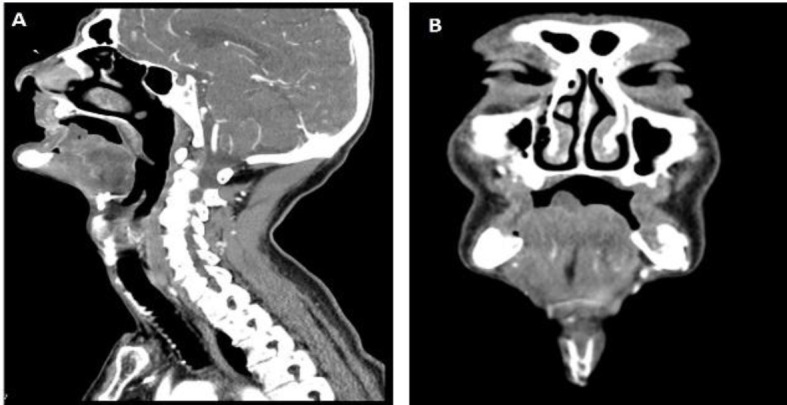

Case report: We present a case of a patient with bilateral necrosis of the anterior third of the tongue, occurring 3 years after chemoradiotherapy treatment for squamous cell carcinoma of the floor of the mouth. Contrast-enhanced CT scan showed multiple areas of stenosis concerning both external carotid arteries and their branches, and total opacification of lingual arteries. Conservative management was performed, with auto-amputation on the fifth day, which allowed healing by secondary intention.